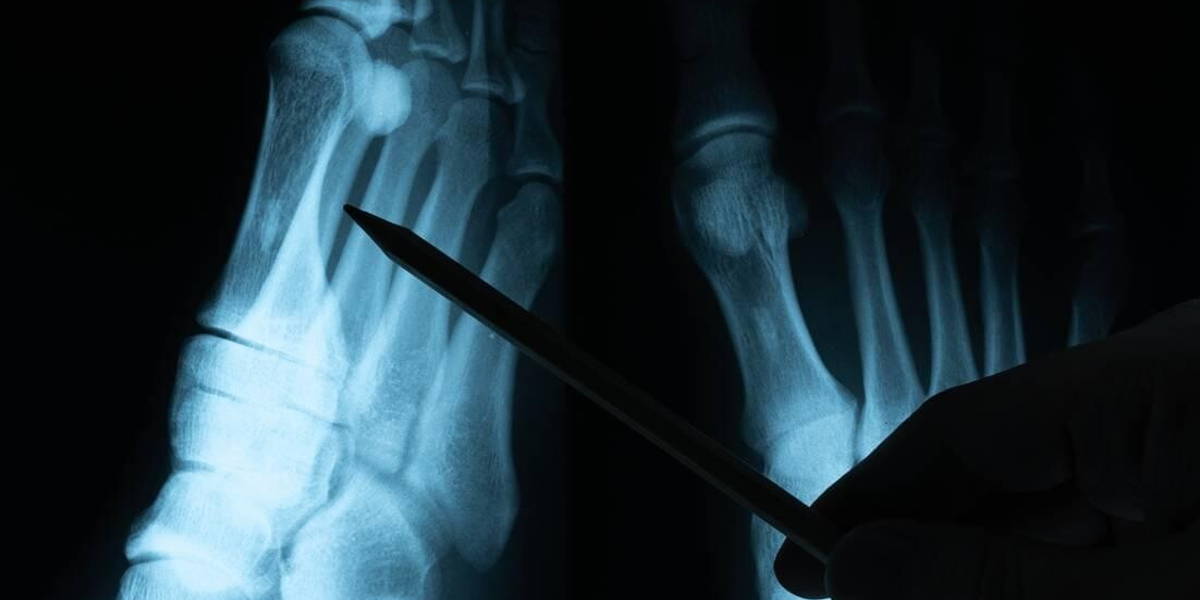

Het ETZ (Elisabeth-TweeSteden Ziekenhuis) maakt de komende drie maanden op proef gebruik van een kunstmatige intelligentie (AI)-toepassing voor het stellen van de juiste diagnose bij een botbreuk. Dagelijks maken de radiologen van het Tilburgse ziekenhuis circa honderd röntgenfoto’s om te bepalen of iemand een botbreuk heeft. De AI-toepassing BoneView is volgens het ETZ een primeur voor Nederland.

Bij een analyse kan BoneView één van de volgende uitkomsten geven: fractuur, géén fractuur of twijfel. Bij verreweg de meeste boordelingen is het algoritme zeker van een fractuur. In dat geval toont de software met een vaste lijn op de foto aan waar de fractuur zich bevindt. Als BoneView twijfelt, wordt dat door de software met een stippellijn op de foto gemarkeerd.

Ranschaert: "Bij zo’n twijfelgeval moet de specialist zelf nog controleren of er bij dat stippellijntje wel of niet sprake is van een fractuur", verklaart. In elk geval moet de radioloog altijd het definitieve verslag maken, dat betekent dat alle foto’s worden nagekeken. Door de proef moeten de radiologen, röntgenlaboranten en alle andere artsen meer ervaring krijgen met de betrouwbaarheid van het algoritme.” BoneView beoordeelt in minder dan drie minuten een foto. Op het moment dat de specialist de foto onder ogen krijgt, heeft het algoritme de analyse al gedaan.